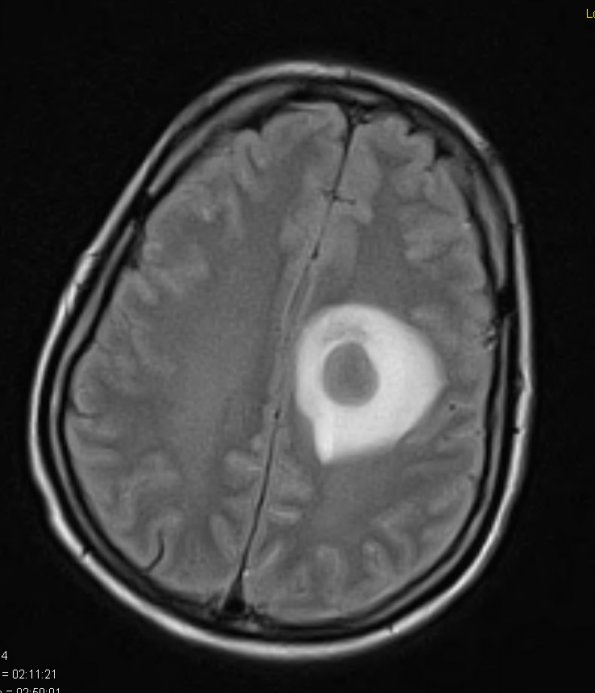

Washington University Experience | INFECTION | Bacteria | Abscess | Abscess, Subacute - Chronic | 13A1 Abscess (Case 13) FLAIR 1 - Copy

13A1 Abscess (Case 13) FLAIR 1 - Copy

13A1 This single mass has induced a great deal of surrounding edema